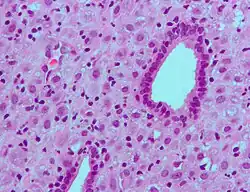

Micrograph showing decidualization of the endometrium due to exogenous progesterone (oral contraceptive pill). H&E stain.

ESCs are the connective tissue cells of the endometrium that are fibroblastic in appearance. However, decidualization causes them to swell up and adopt an epithelial cell-like appearance due to the accumulation of glycogen and lipid droplets. Furthermore, they begin secreting cytokines, growth factors, and proteins like IGFBP1 and prolactin, along with extracellular matrix (ECM) proteins such as fibronectin and laminin. The increased production of these ECM proteins turns the endometrium into the dense structure known as the decidua, which produces factors that promote trophoblast attachment and inhibit overly aggressive invasion.[7]